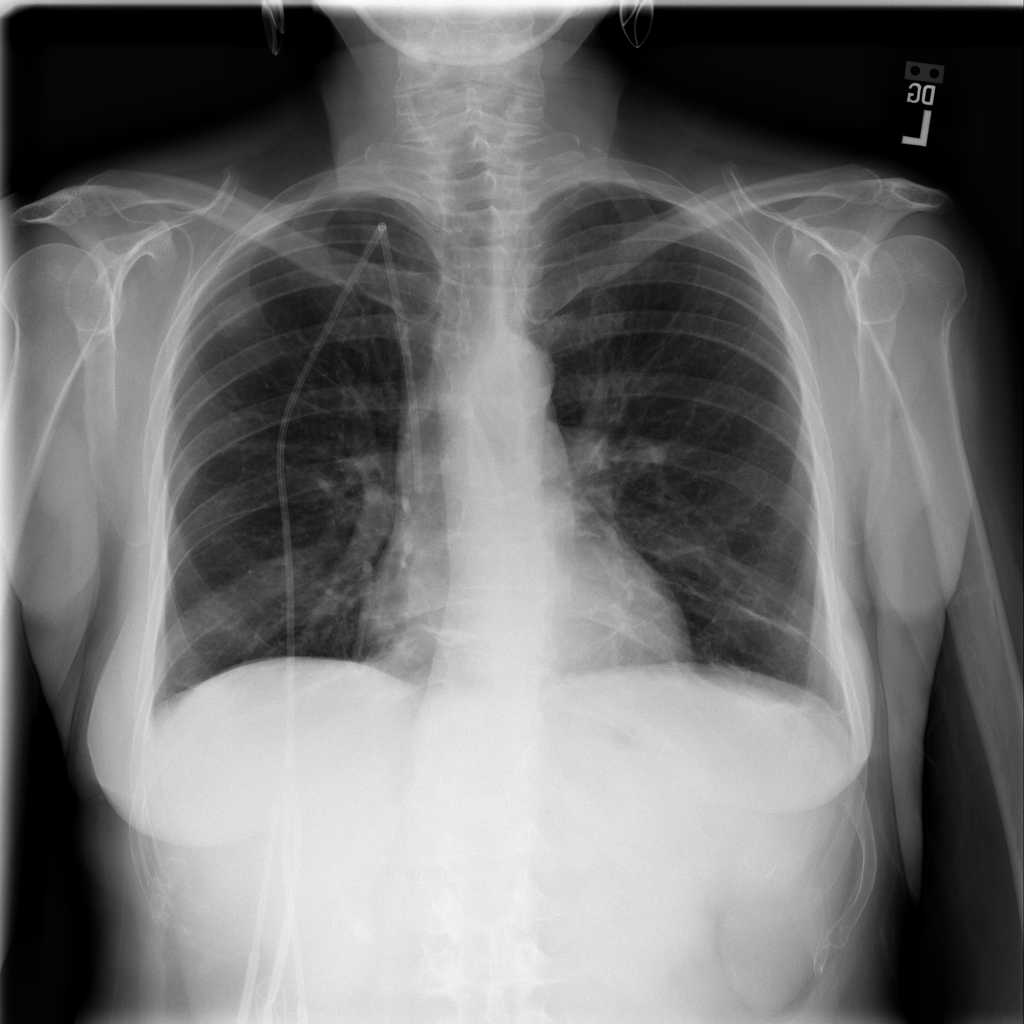

PAT-06B1 · IMG-021Fibrosis

PAT-06B1 · IMG-021

AP